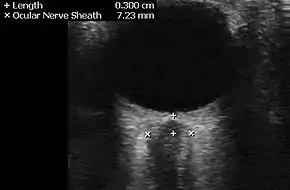

Neuroimaging, usually with computed tomography (CT/CAT) or magnetic resonance imaging (MRI), is used to exclude any mass lesions. In IIH these scans typically appear to be normal, although small or slit-like ventricles, dilatation and buckling[17] of the optic nerve sheaths and "empty sella sign" (flattening of the pituitary gland due to increased pressure) and enlargement of Meckel's caves may be seen.

An MR venogram is also performed in most cases to exclude the possibility of venous sinus stenosis/obstruction or cerebral venous sinus thrombosis.[5][7][8] A contrast-enhanced MRV (ATECO) scan has a high detection rate for abnormal transverse sinus stenoses.[14] These stenoses can be more adequately identified and assessed with catheter cerebral venography and manometry.[15] Buckling of the bilateral optic nerves with increased perineural fluid is also often noted on MRI imaging.